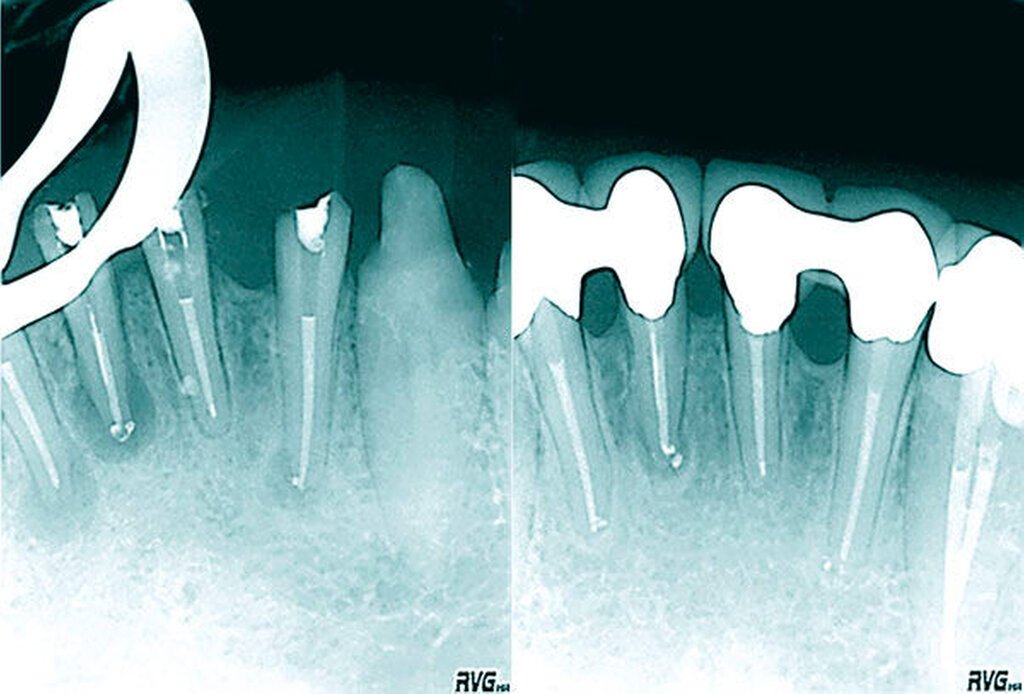

Die geringe Größe der klinischen Zahnkrone mit maximal 4 bis 5 mm Breite oder eine gedrehte oder gekippte Zahnstellung allein sind große klinische Herausforderungen, das Wurzelkanalsystem im Fall einer endodontischen Behandlung vollständig darstellen zu können. Die tiefen Aufteilungen als Folge einer Dentinbrücke lassen sich ohne Nutzung eines Dentalmikroskops nur mit erheblichem Zahnhartsubstanzverlust darstellen, so dass der Langzeiterhalt des Zahnes mit der erhöhten Gefahr einer Vertikalfraktur kompromittiert wird. Bei alters- oder reizbedingten Obliterationen des Wurzelkanalsystems erhöht sich darüber hinaus das Risiko einer lateralen Wurzelperforation oder Instrumentenfraktur [Kvinnsland, 1989] (Abbildungen 16a und 16b).

Die mikrobielle Infektion und die unvollständige Wurzelkanalbehandlung lassen sich durch allein chirurgisch resektive Verfahren nicht korrigieren (Abbildungen 17 bis 20). Sofern eine retrograde Präparation, Desinfektion und ein bakteriendichter Verschluss gelingen, kann die Infektion eingeschlossen werden. Die orthograde Revision im Verlauf der antimikrobiellen Therapie ermöglicht unter mikroskopischer Sicht eine vollständige Reinigung und Desinfektion (Abbildungen 15 bis 17).

Zweidimensionale Röntgenaufnahmen ermöglichen auch bei exzentrischer Projektion keine sichere Differenzierung zwischen ein- und mehrkanaligen Wurzelkanalsystemen unterer Frontzähne. Lediglich eine Kontinuitätsunterbrechung im Wurzelkanalverlauf kann als ein Hinweis für eine Aufteilung des Wurzelkanalsystems genutzt werden [Hülsmann & Schäfer, 2007]. DVT-Aufnahmen können die diagnostische Sicherheit zur präoperativen Analyse des Wurzelkanalsystems verbessern, bieten aber systembedingt keine absolute Sicherheit in der Differenzierung mehrkanaliger Wurzelkanalsysteme [Paes da Silve Ramos Fernandes et al., 2014]. Insbesondere die in einwurzeligen Zähnen vorhandene Dentinbrücke 3 mm unterhalb der Schmelz-Zement-Grenze ist in etwa 50 Prozent der Fälle für eine Unterteilung in zwei Wurzelkanäle verantwortlich. Die Dentinbrücke ist geringer mineralisiert, weist einen geringeren Röntgenkontrast auf und lässt sich deshalb radiologisch schwer darstellen.

Die Nutzung optischer Vergrößerungen mit zusätzlicher Lichtzufuhr (optimal Xenonbeleuchtung) zur sicheren und minimalinvasiven Darstellung des Wurzelkanalsystems wird empfohlen [AAE Position Statement, 2012]. Bei der Ausdehnung der endodontischen Zugangskavität sollte die Inzisalkante bis zur labialen Begrenzung einbezogen werden [Arnold, 2010]. Insbesondere im Fall einer mikrobiellen Infektion sollte aufgrund der komplexen Aufgabenstellung den Patienten eine Behandlung unter Sicht mit einem Dentalmikroskop empfohlen werden, um das Risiko einer fortbestehenden Infektion und den Zahnhartsubstanzverlust zu minimieren [Xu, 2008].